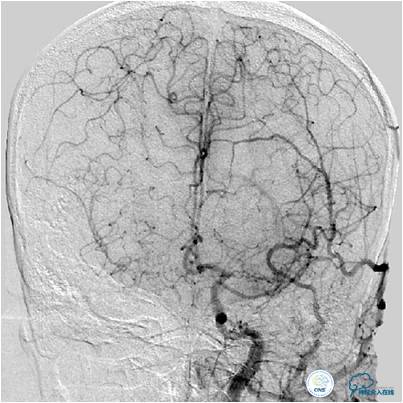

患者入院后,完善颅内CTA(图1)及血管造影(图2~3)检查,发现右侧颈内动脉颅内段闭塞,右侧大脑前动脉依靠左侧颈内动脉系统通过前交通动脉供血,右侧大脑中动脉供血区则依赖于右侧大脑前动脉(ACA)软脑膜代偿供血,左侧大脑中动脉闭塞,依靠一少见血管代偿供血,该血管起自左侧大脑前动脉A2段起始部,代偿供应左侧大脑中动脉供血区。由于该患者灌注CT(图4)未见明显低灌注区,遂给予患者抗血小板、降脂及控制危险因素治疗出院。出院后电话随访未再出现过上述症状。

图3B:左侧颈内动脉造影动脉晚期提示双侧大脑半球染色尚可,右侧大脑中动脉供血区由右侧大脑前动脉的软脑膜动脉代偿。